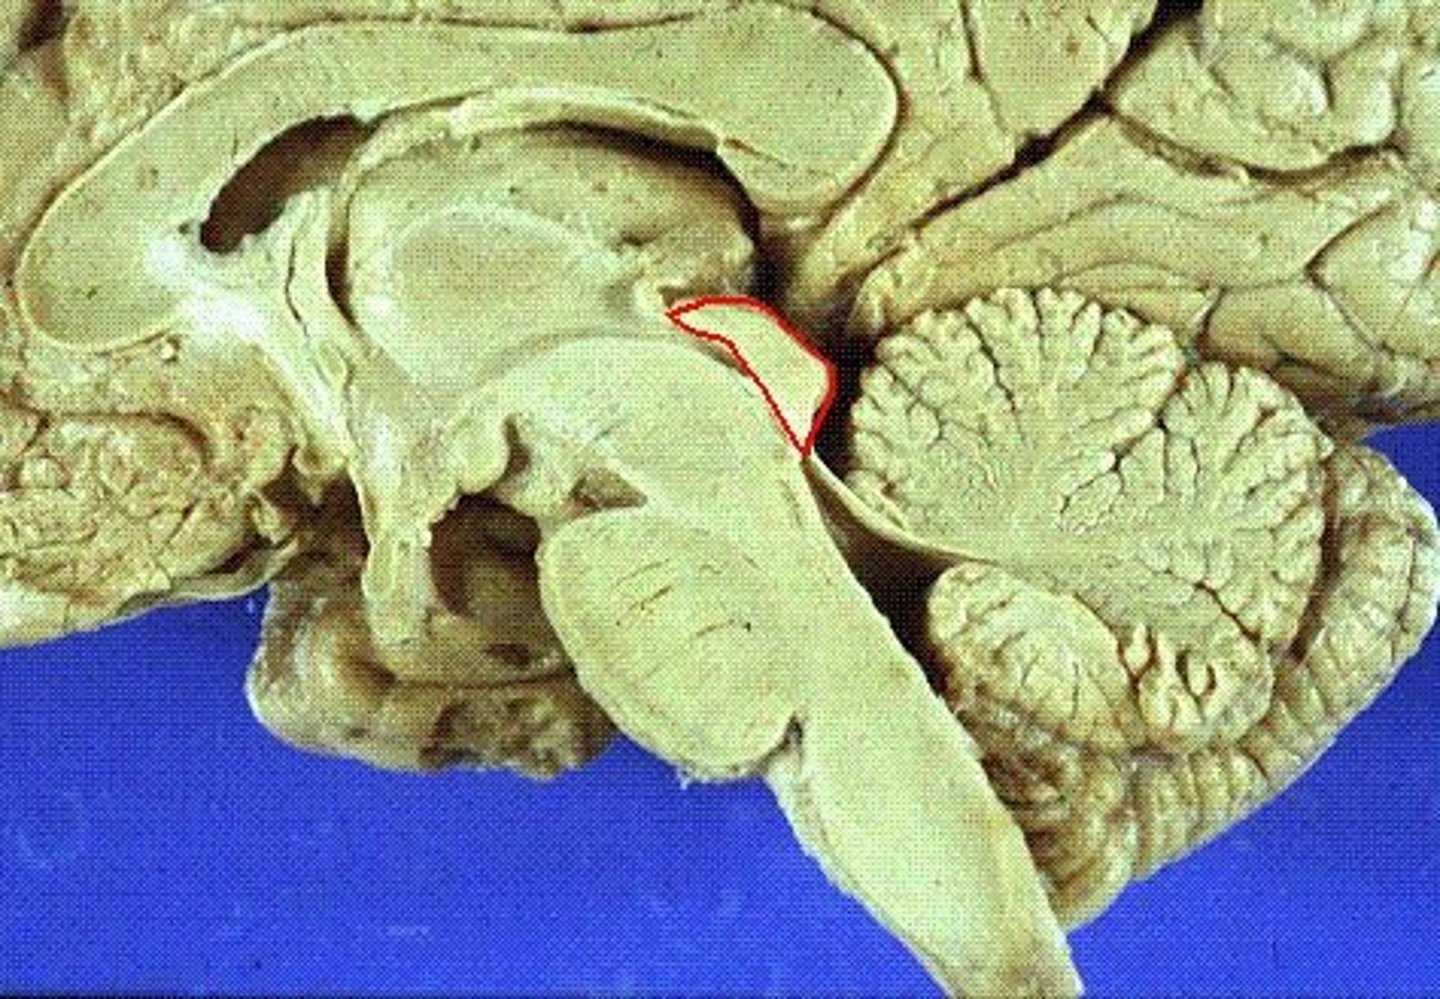

tentorium cerebelli

2nd largest, crescent-shaped, separates cerebrum (occipital lobes) from cerebellum (arrow #5)

falx cerebelli

seperates the two hemispheres of the cerebellum. it lies inferior to the tentorium cerebelli, separating cerebellar hemispheres (arrow #7)